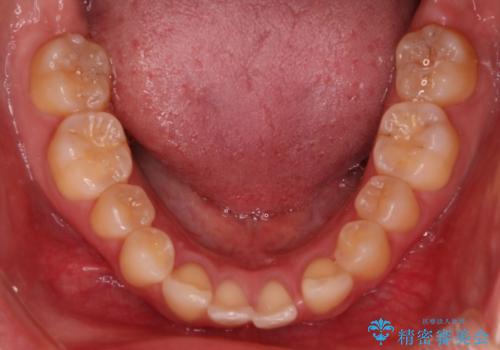

- 患者様は、上下の噛み合わせのバランスが悪く、特に上顎の前歯の突出を気にされて来院されました。診査の結果、下顎の歯並びに合わせて上顎を後方へ移動させる必要があると判断し、上顎の小臼歯2本を抜歯することを提案しました。目立たない矯正を希望されたため、**インビザライン(マウスピース矯正)**を選択。計画的にスペースを作りながら、バランスの取れた歯並びを目指しました。

治療はまず、上顎の小臼歯を2本抜歯し、そのスペースを利用して前歯を後方へ移動させました。インビザラインはアタッチメントを併用し、より効率的に歯を動かせるよう調整。定期的なチェックとアライナーの交換を続け、約3年かけて理想的な歯並びと噛み合わせを実現しました。治療後はリテーナーを使用し、安定した状態を維持。患者様からは「口元がスッキリし、横顔の印象も変わった」と嬉しいお声をいただきました。